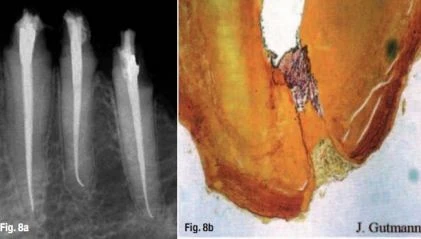

Quan điểm thứ nhất khẳng định chắc chắn rằng nên lựa chọn cách điều trị lấy tủy khi xác định điểm chóp cuối cùng nằm tại lỗ chóp sinh lý (Hình 8a & b). Chúng tôi hiện sử dụng phương pháp này, nó đã được chấp nhận rộng rãi ở đa số các trường nha khoa và các nhà lâm sàng Châu Âu, trong hầu hết mỗi trường hợp, ở bất kỳ tổn thương nào thì theo nguyên tắc sinh học và y học cơ bản: “càng ít mô cần chữa trị, thì việc điều trị càng tốt”.

các ít mô cần được chữa

Hình 8a & b: Càng ít mô cần được chữa thì việc chữa trị tiên lượng càng tốt: hình ảnh kiểm tra trên X-quang sau 12 tháng (a); lành thương ở vùng chóp và hình thành cầu xi măng (b)